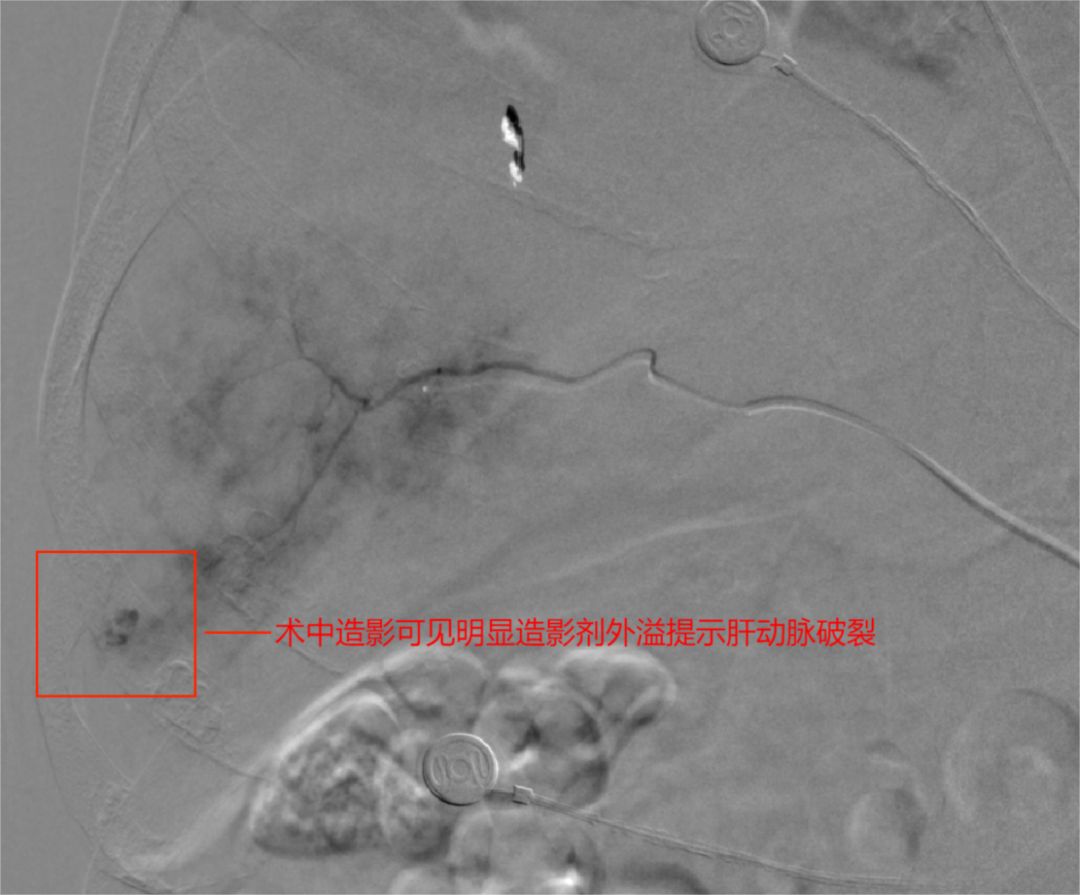

(1)造影检查:采用Seldinger技术经右股动脉插入动脉导管鞘及导管,使用高压注射器,以猪尾导管作腹主动脉造影。主动脉造影的目的是发现肝以外的其他出血部位,以及确定肝动脉的解剖位置。如有肝损伤,通常可见到以下征象:①造影剂外渗征象;②肝动脉中断征象,为血管断裂后血凝块形成,又在断裂处堵塞断裂血管所致;③血管远端受压达不到肝的缘,为包膜下血肿压迫所致;④血管走向改变,包括聚拢、撑开、扭曲等征象,为肝内血肿所造成⑤实质期肝脏显影不均匀,肝内血肿显示为充盈缺损;⑥动-静脉瘘或肝动脉-门静脉瘘形成或假性动脉瘤形成者。当出现上述造影表现时,进一步作选择性腹腔动脉和肠系膜上动脉造影。对疑有出血部位者,尽量将导管超选择性插入相关动脉分支,作超选择性血管造影,以明确肝血管损伤的部位、程度和性质,确定拟栓塞的靶血管。

(2)动脉栓塞治疗:①肝损伤部位和拟栓塞的靶血管确定后,超选择性插入相关动脉主干近端,将明胶海绵根据需要剪成粗细不同的颗粒[直径1mmX(1~3mm)]或条块(lmm lmmX5mm),装入混有造影剂及庆大霉素的注射器内并摇匀,在透视监控下缓慢、少量、分次注入损伤血管,当血管血流明显缓慢或铸形,提示出血动脉已闭塞,再造影复查见造影剂外溢消失。